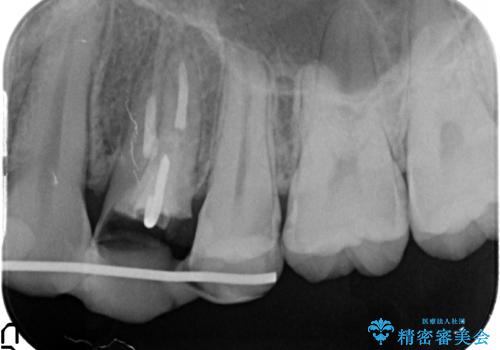

左上4の補綴物を除去したところ縁下歯質だったため、歯牙の挺出を提案し行いました。

挺出終了後は歯肉切除および骨外科により歯周組織を整え、オールセラミッククラウンによる補綴を行いました。